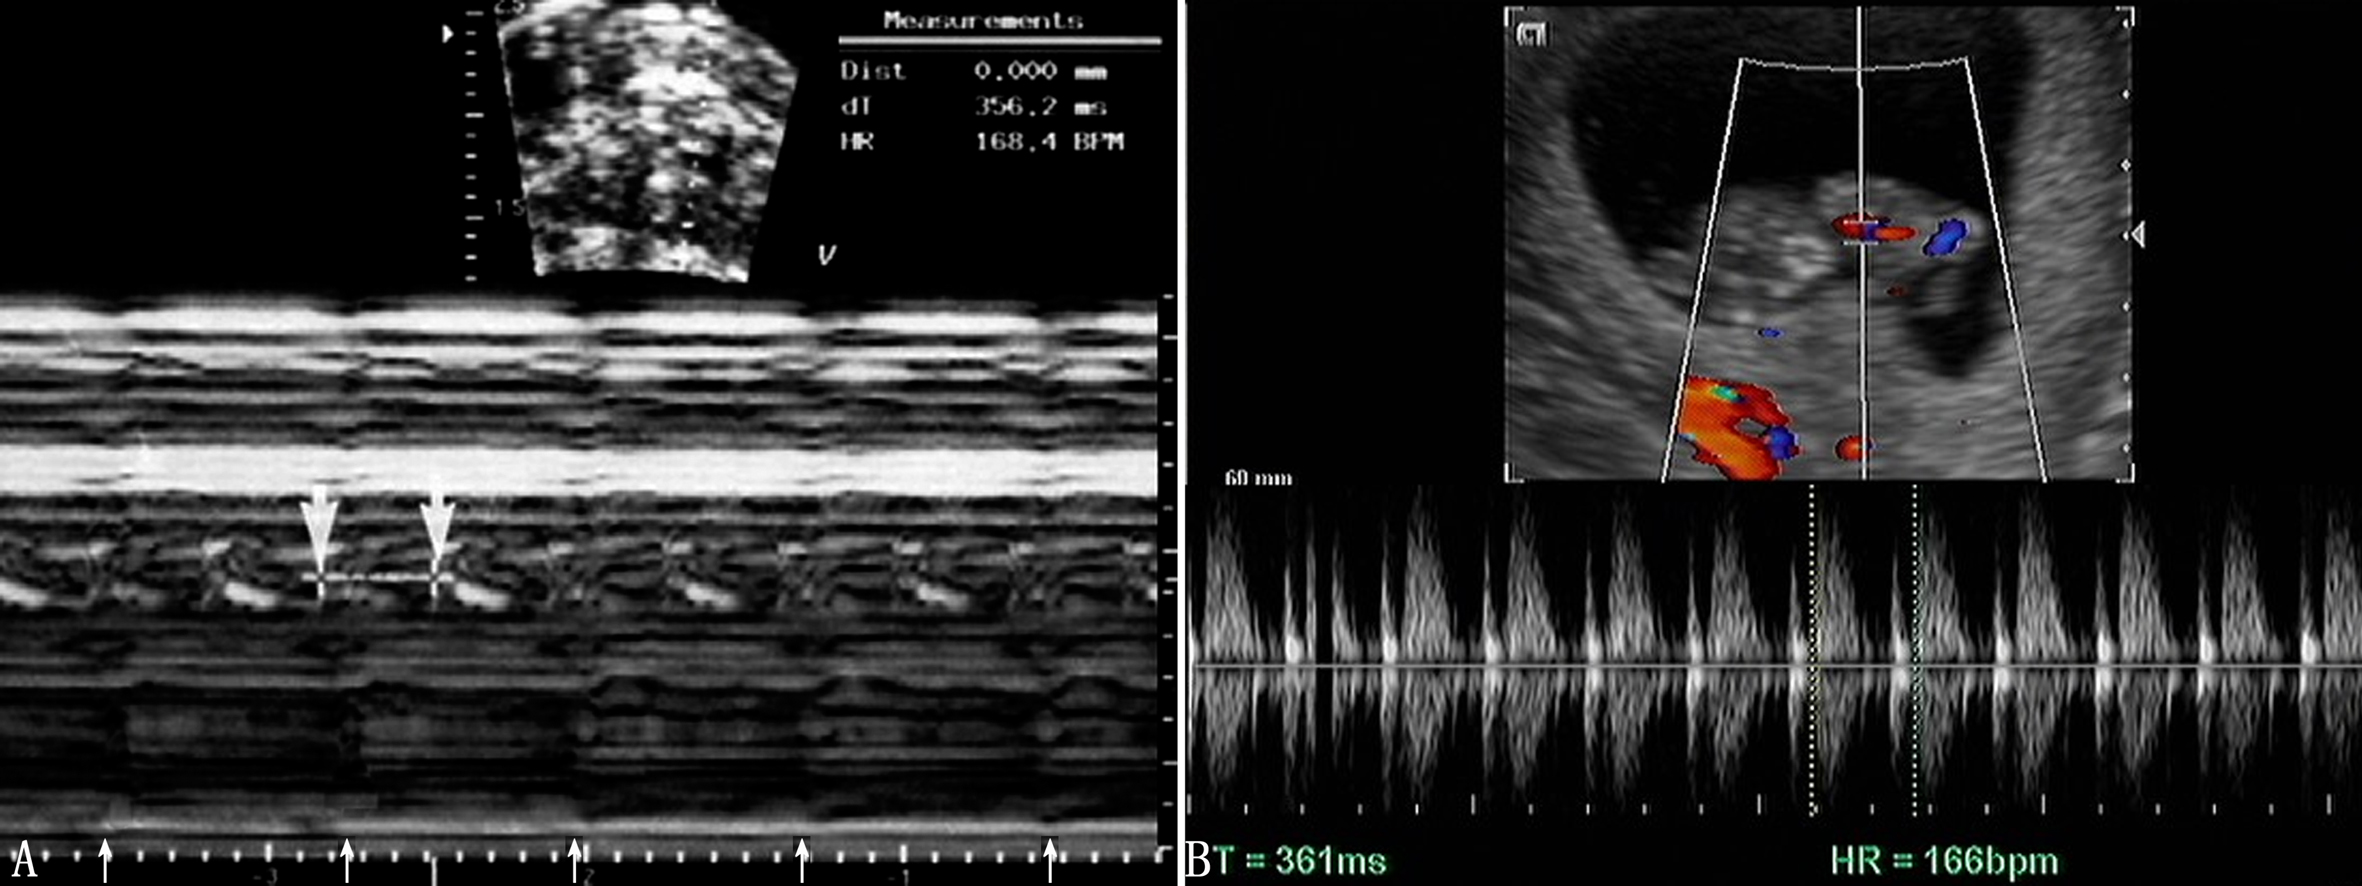

胎儿心脏发生于妊娠后的第18~19天,第21~22天以后心管形成并开始跳动,此时正值停经后的第35~36天,经阴道超声检查即可显示心管活动,经腹超声检查显示的要晚一些。一般在第5周末或第6周、在显示胚胎的同时可显示心管的活动(图1)。二维超声检查显示为快速活动的点状回声,彩色多普勒血流显像检查显示为快速色彩交换的点状回声。

图1早期胎心搏动A:9周胎心搏动(粗箭头,HR168 bpm)和母体活动(细箭头)B:11周胎心血流,HR166BPM